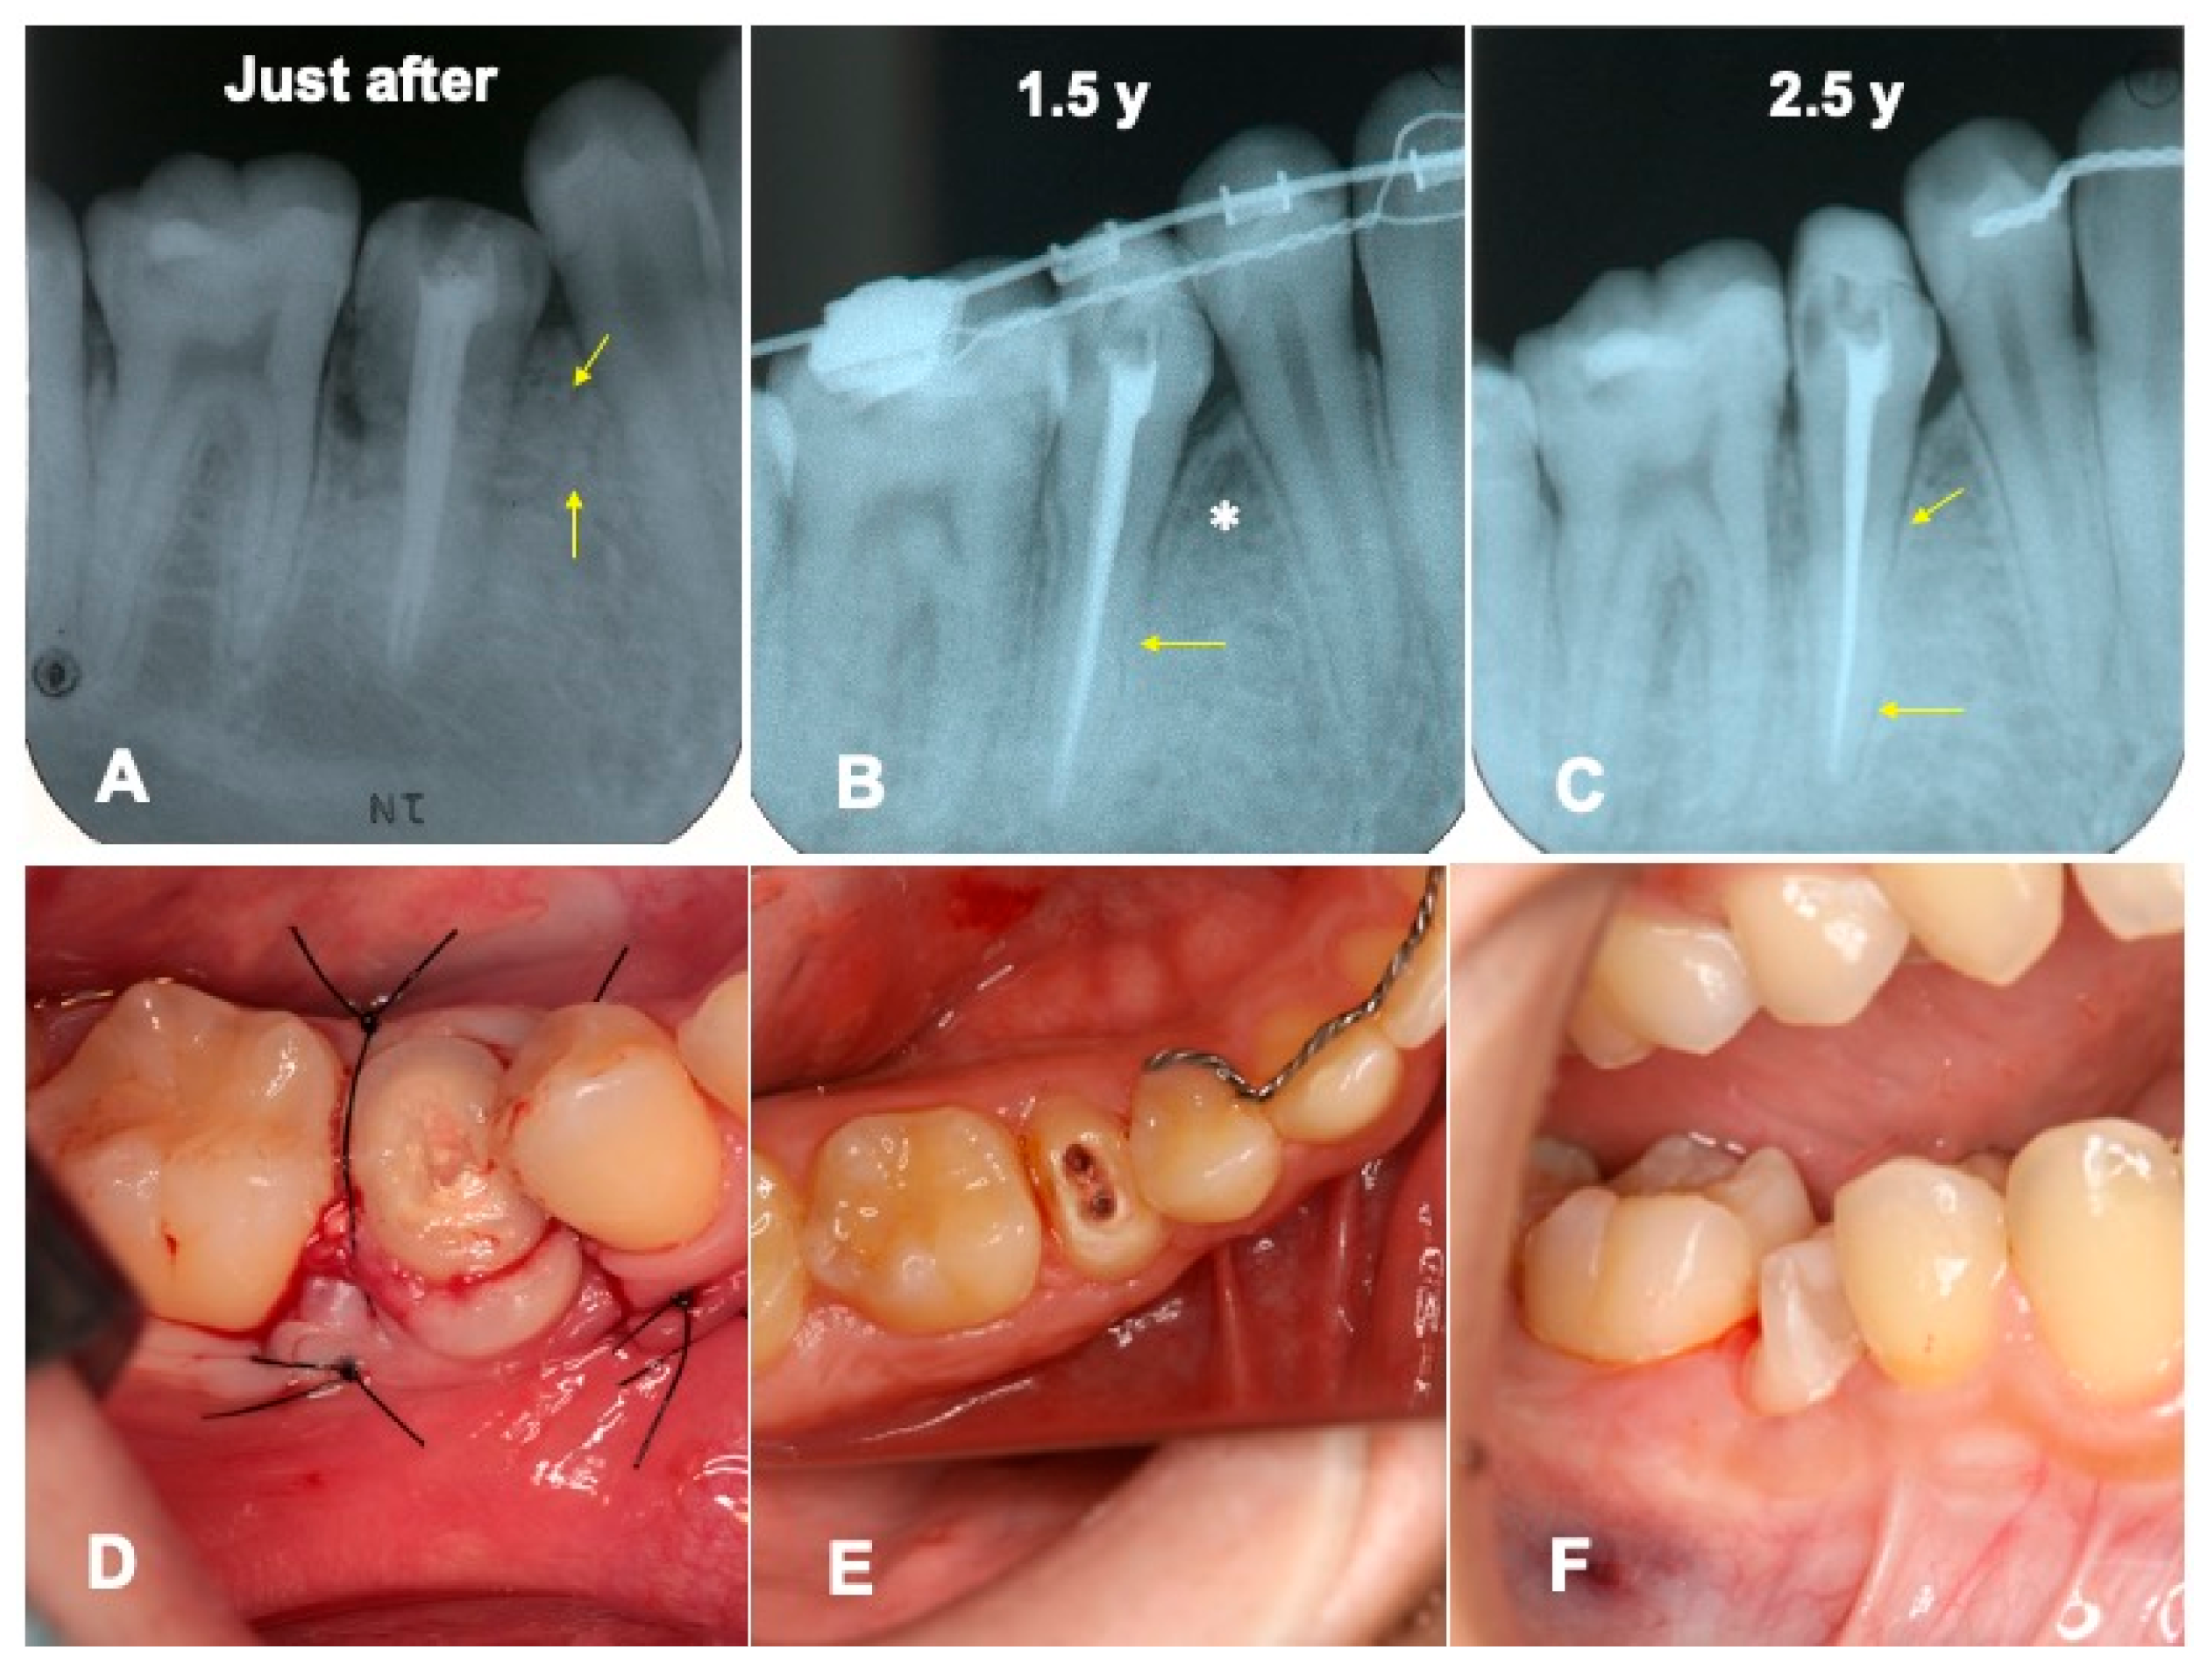

Figure 7.

Dental X-ray and intraoral photos. (A) Appearance just after surgery. Arrows showing pDDM granules. (B) Appearance at 1.5 years. Arrow indicating suspected area after limited root resorption. Totally remodeled bone-like shadow (*). (C) Appearance at 2.5 years. Arrows indicating periodontal ligament space. (D) View just after immediate surgery. (E) View of root and periodontal tissues before being built up. (F) View just after core formation for impression of final ceramic crown. Abutment tooth built up with a direct resin composite core (BeautiCoreSystem®, Shofu Co., Ltd., Kyoto, Japan) with fiberpost (BeautiCoreFiberPost®, Shofu Co., Ltd., Kyoto, Japan).

Just after the surgery, the extracted sockets of the maxillary premolars and the root canal filling of the transplanted tooth were seen clearly (Figure 6A). The grafted pDDM were confirmed as each radiopaque granule (Figure 7A). The transplanted root and bone showed a similar radio-opacity, and a periodontal ligament space was not seen (Figure 6A). After 1.5 year of orthodontic treatment, the periodontal ligament space and alveolar ridge line were observed, and pDDM granules were not seen clearly (Figure 6B and Figure 7B). In addition, all wisdom teeth were already extracted (Figure 6B). A slight curve of the root surface was observed adjacent to a normal periodontal ligament space and the lamina dura during the orthodontic treatments (Figure 7B). The view at 2.5 years shows removal of orthodontic devices, except the mandibular retention wire, and a single standing of the transplanted tooth without wire (Figure 6C and Figure 7C). A continuous periodontal ligament space and lamina dura were found, and root concrescence did not occur (Figure 7C and Figure 8B).

4.4. Root Resorption Subsequent to Transplantation

Three types of root resorption after tooth autotransplantation are classified, as follows: surface resorption, inflammatory resorption, and replacement resorption [11]. Orthodontic rotation for autotransplanted premolars induced a slight surface resorption and a significantly shorter tooth length (mean 1.2 mm) [11]. In this case, a slight root surface resorption of the transplanted tooth was observed during orthodontic movement adjacent to a normal periodontal ligament space and the lamina dura (Figure 7B). The rotation might temporarily induce a limited surface resorption.